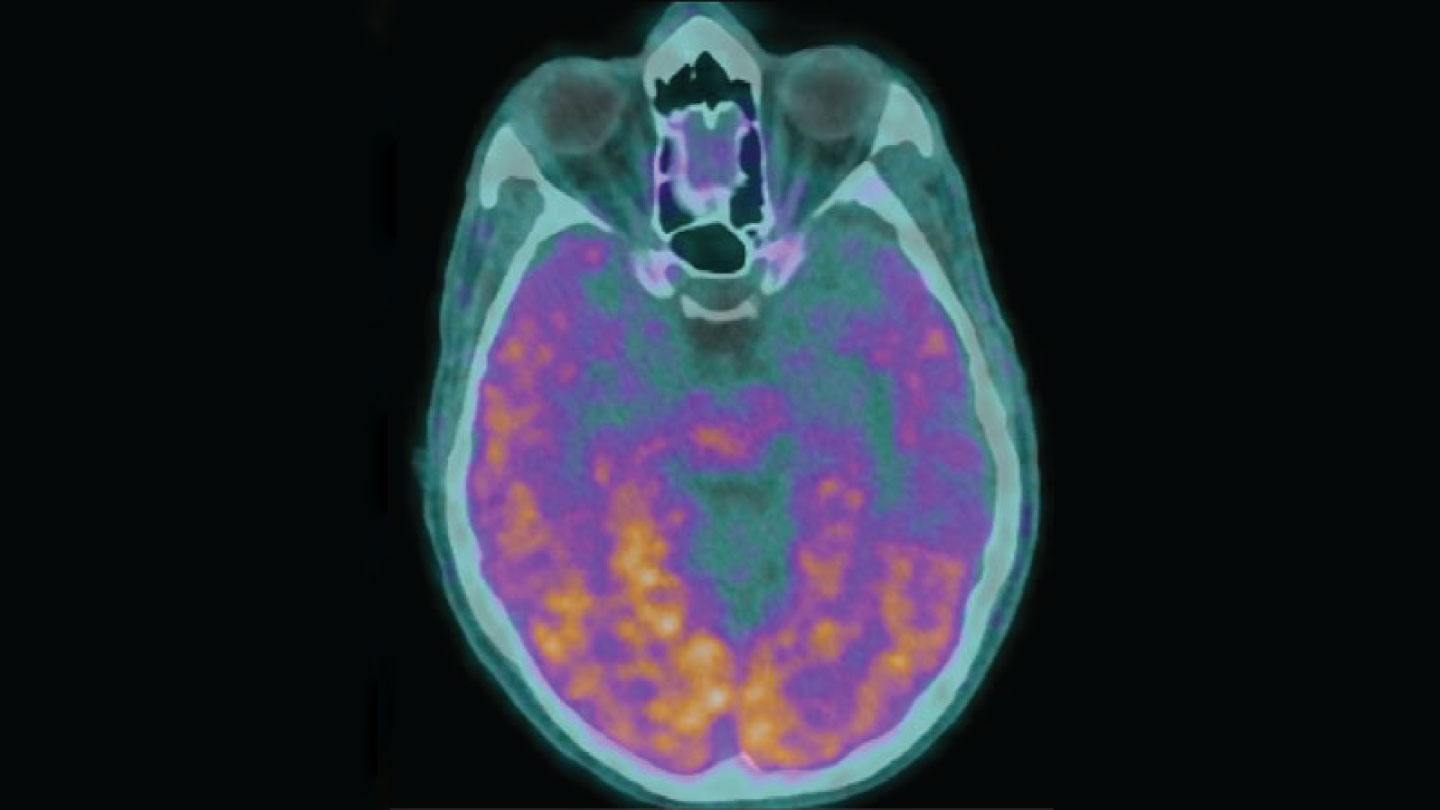

Alzheimer transmitted?

Alzheimer’s disease is not contagious in everyday life, but in extremely rare conditions, it can be spread from one person to another (Sn: 2/24/24, p. 6). Five people who in childhood received contaminated growth hormone injections later developed early Alzheimer’s early chances because hormones were painted with amyloid-beeta, a protein of which is associated with the disease, researchers say. But it is not yet clear if the growth hormones are blamed, other experts notice. Perhaps the health conditions those hormones were aimed at treating or other medical procedures led to the development of Alzheimer’s in these patients.